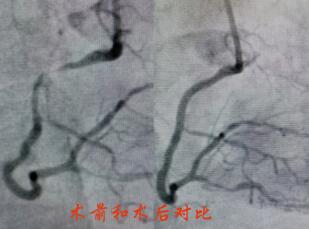

造影提示陶奶奶冠脈病情較重,左主干+三支病變,屬于非常復雜也極為危險的冠脈病變。經過心內科介入團隊和家屬的反復溝通,立即對陶奶奶的右冠進行了支架置入,術后陶奶奶的胸痛很快緩解,并經過數(shù)天的后續(xù)治療,順利出院。

春節(jié)剛過,陶奶奶的孩子們帶著陶奶奶再次來到了江寧中醫(yī)院心內科準備拆除這顆潛在的“致命炸彈”。韋鋒主任反復研究陶奶奶的前期手術影像,心中擬定著多個手術方案。經過充分準備,2月15日,韋鋒主任再次為陶奶奶進行了介入手術。術中通過血管內超聲(IVUS)精細、準確評估陶奶奶的冠脈病變情況,發(fā)現(xiàn)陶奶奶的左主干最小管腔面積僅僅3.7mm2,;前降支近段全程鈣化,最嚴重處呈270度的環(huán)形鈣化,最小管腔面積僅僅2.1mm2;回旋支開口正常,回旋支近端最小管腔面積1.8mm2。韋鋒主任根據(jù)IVUS的結果,改變了原來擬定的DKCRUSH術式,決定采用藥物球囊和藥物涂層支架相結合的方式處理病變(LCX藥物球囊,LM-LAD植入支架),經過近2個小時的手術,陶奶奶的冠脈血管又“完美”地回來了。